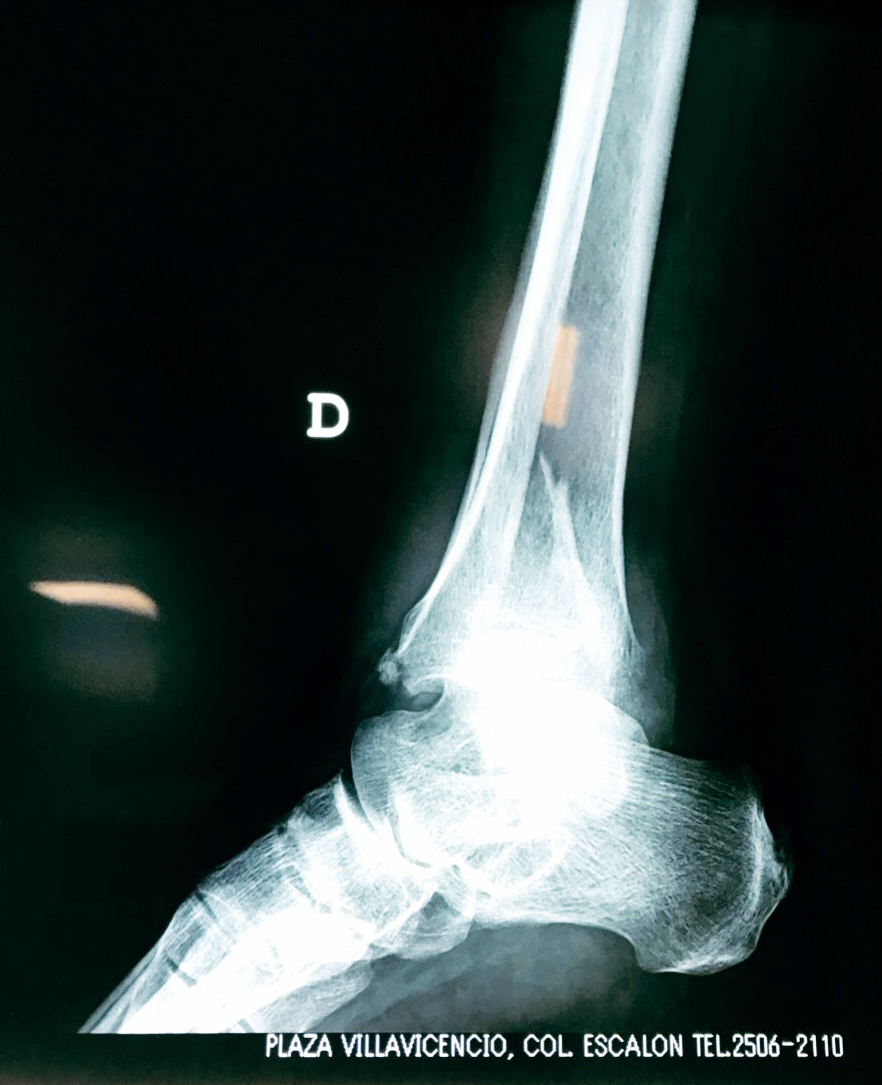

Una fractura de tobillo es la rotura de uno o más de los huesos del tobillo. Estas fracturas pueden ser:

Algunas fracturas de tobillo pueden requerir cirugía si:

- Los extremos de los huesos están desalineados entre sí (desplazados).

- La fractura se extiende hasta la articulación del tobillo (fractura intra-articular).

- Los tendones o ligamentos (tejidos que sujetan los músculos y los huesos entre sí) están rotos.